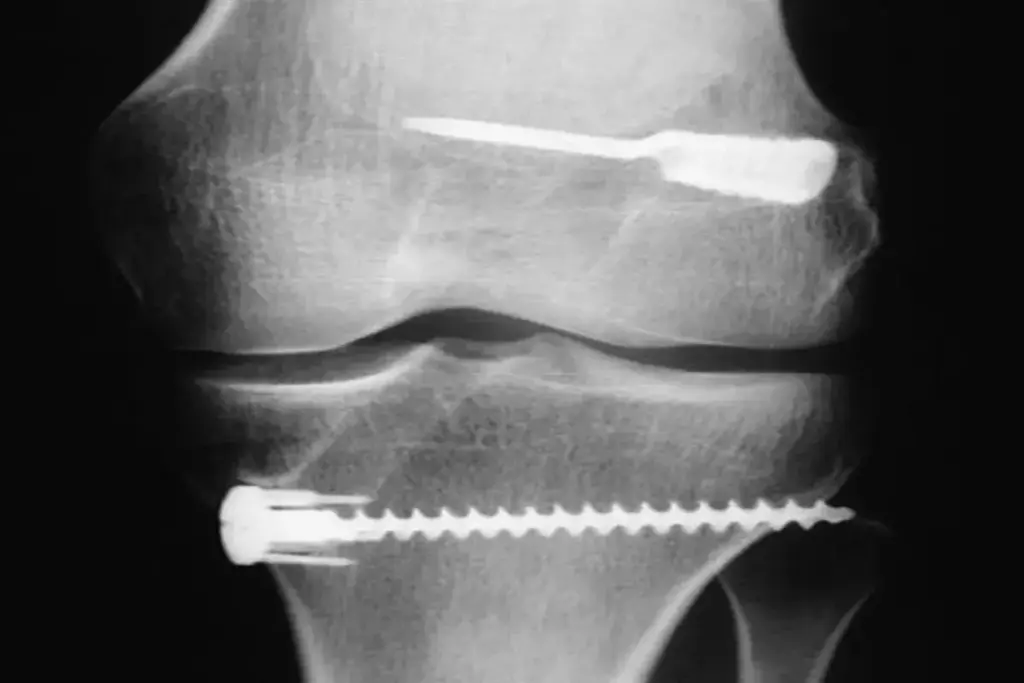

Bone-Patellar Tendon-Bone (BPTB) Autografts

BPTB autografts are a common choice for ACL reconstruction. They take a piece of the patellar tendon and bone from the patella and tibia. This graft heals fast and strong, helping you recover quickly.

But, BPTB autografts can cause pain in the front of the knee and when kneeling. They are strong at first but might not heal as well as other grafts.